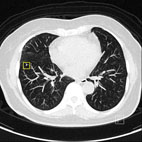

其中,雙射源電腦斷層掃描儀,其輻射量低、檢查速度快,專長於心臟血管檢查及低劑量肺癌篩檢。就心臟冠狀動脈檢查而言,不需任何藥物降低心跳次數,便可獲得清晰且具診斷價值的高解析度影像;低劑量肺癌篩檢,可發現4mm以下的微小病灶。

肺部電腦斷層掃描使用CAD功能所偵測到的影像,經放大後發現其為長3.85mm寬3.15mm的小結節。